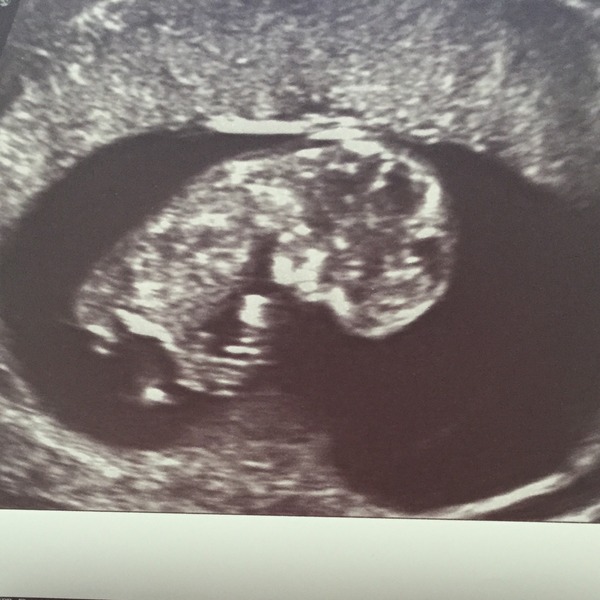

ATrueNerd · 09/07/2015 14:12

Here's the pic Smile Not much to see, apparently my bladder was full (I had only been to the loo 5 mins earlier!) which made it harder to see but she got the measurements ok x

ATrueNerd- amazing picture. You must feel so relieved :) It was internal I guess?

Yes creme, it was dildo cam! Blush doesn't hurt at all though. Such a relief, and the scan lady was lovely and said straight away "one pregnancy with a heart beat" the lady at my 5 weeks one was just silent for ages which freaked me out! I've booked a private one for 9 weeks. Will be thinking of you on Saturday xx